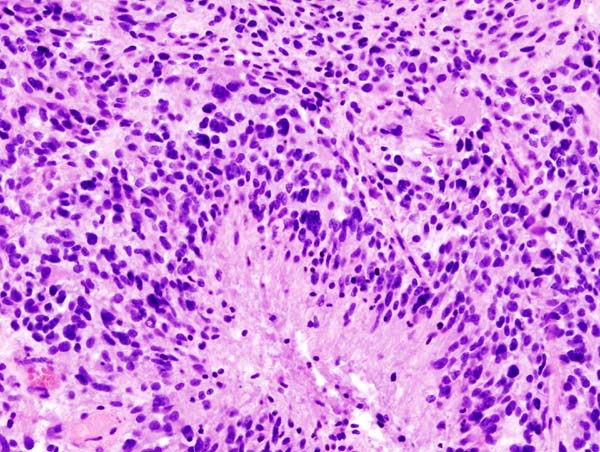

; CT

: 단순 CT에서는 종양 실질이 고흡수역, 주변의 괴사부나 낭포는 저흡수역으로 조영된다. 조영제를 사용한 조영 CT에서는 종양 실질이 불균일하게 증강된다.

- CT: 단순 CT에서는 종양 실질이 고흡수역, 주변의 괴사부나 낭포는 저흡수역으로 조영된다. 조영제를 사용한 조영 CT에서는 종양 실질이 불균일하게 증강된다.